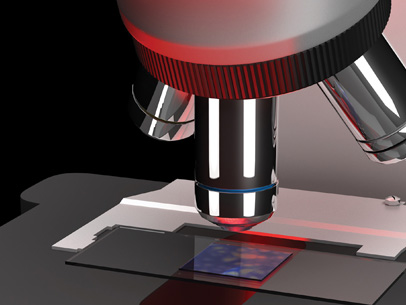

Mapping Biology with Spatial Omics

A recent explosion of spatial profiling techniques—largely enabled by optics and photonics technologies—gives biologists an unprecedented view of single cells and tissues.

A Live Look at the Reproductive System

At the upcoming Optica Biophotonics Congress, Irina Larina will talk about dynamic optical coherence tomography for in vivo imaging of the fallopian tubes.